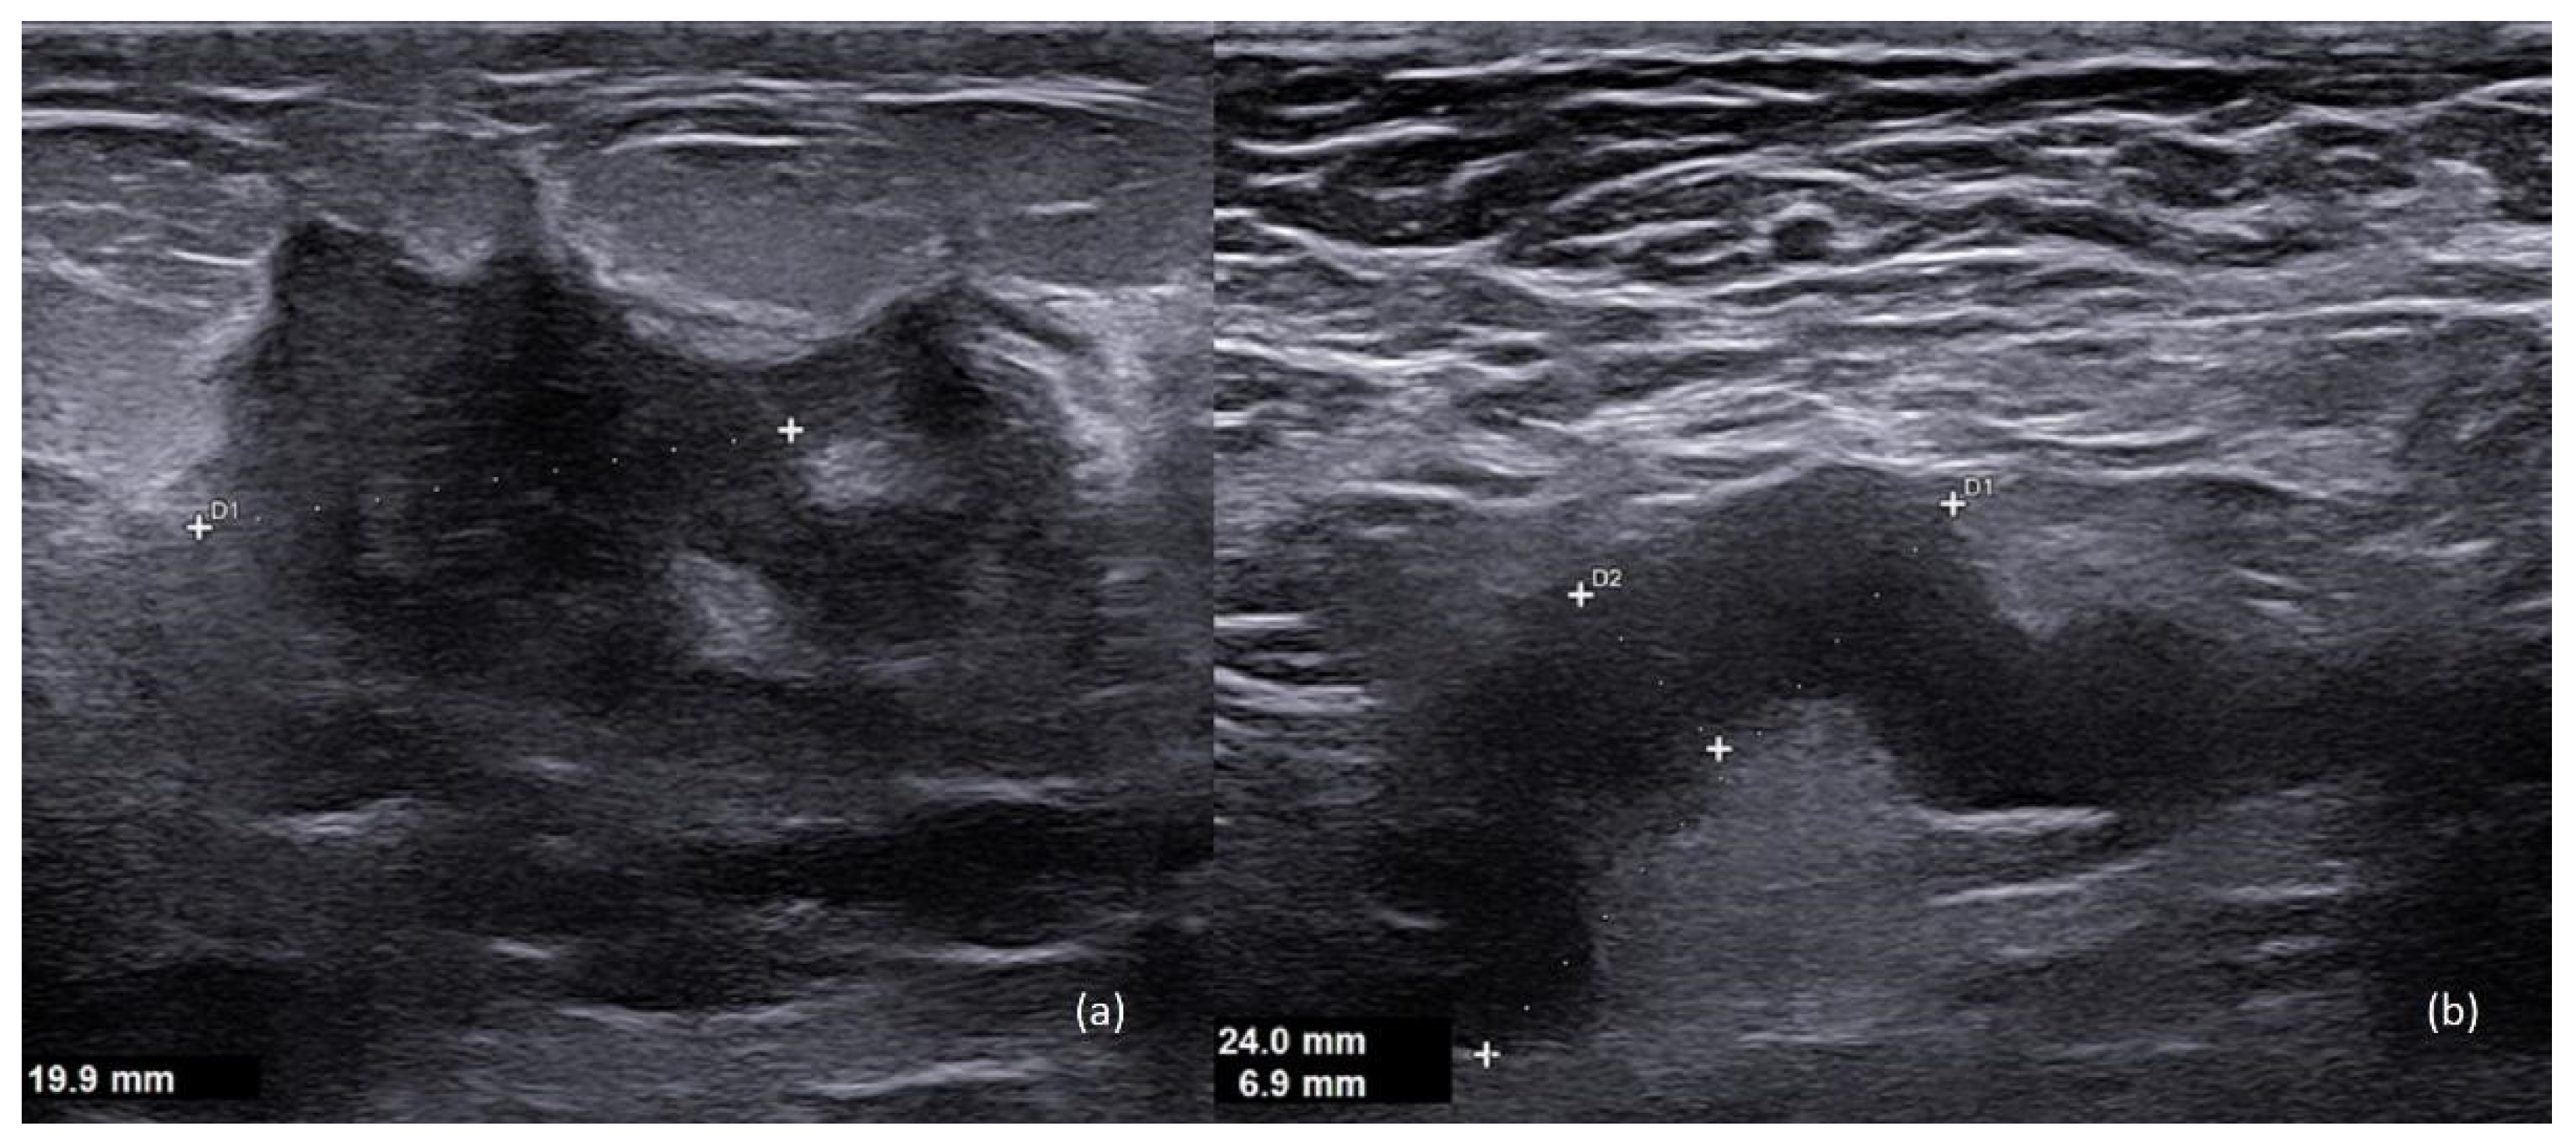

4. Imaging

- Ayyappan, A.P.; Kulkarni, S.; Crystal, P. Pregnancy-associated breast cancer: Spectrum of imaging appearances. Br. J. Radiol. 2010, 83, 529–534. [Google Scholar] [CrossRef] [PubMed]